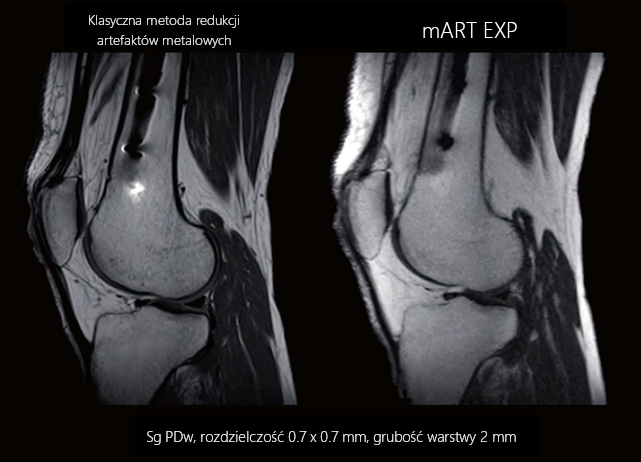

Technika redukcji artefaktów metalowych – mART EXP (EXPansion)